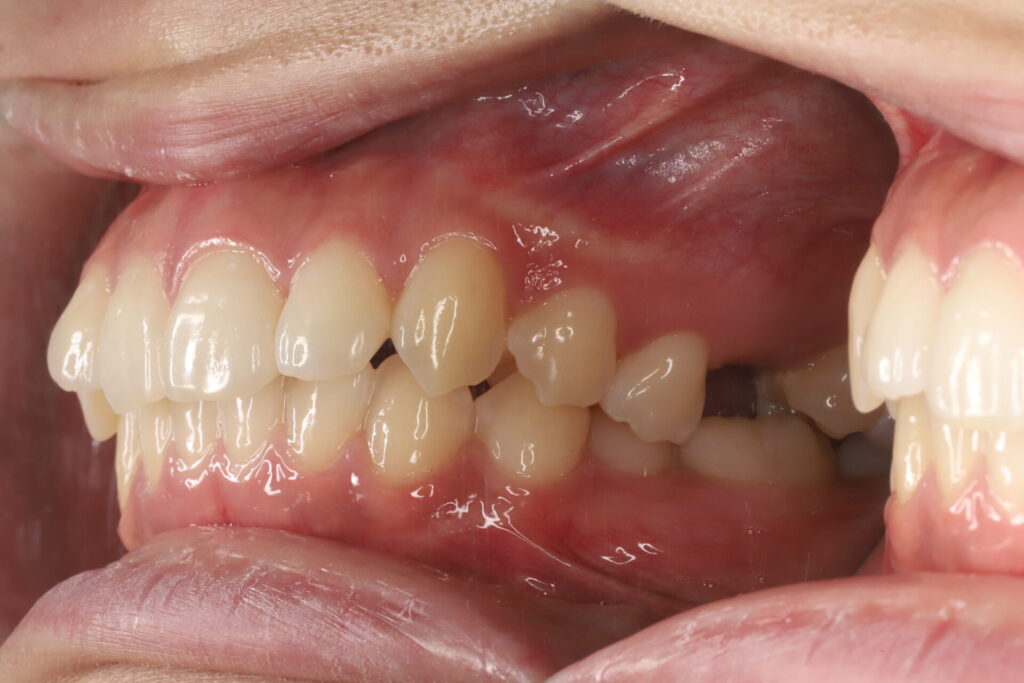

骨格分析に基づき、欠損部にインプラントを入れず、インビザライン(マウスピース矯正)でスペースを閉鎖しながら歯並びと咬合を同時に改善しました。

他院で「インプラントは難しい」と説明を受けた20代女性から、インプラント希望でご相談。精査の結果、矯正でのスペース閉鎖が適応と判断しました。

- 結果:スペース閉鎖+配列改善により、見た目・発音・咬合安定・清掃性が向上